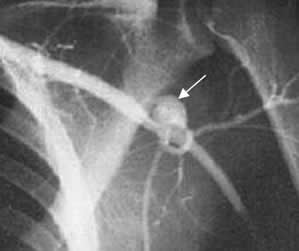

Fig 142 E. Seudoaneurisma.

Arteriografía. Herida por arma cortopunzante axilar. Se identifica imagen sacular que se dirige superiormente y corresponde a seudoaneurisma.